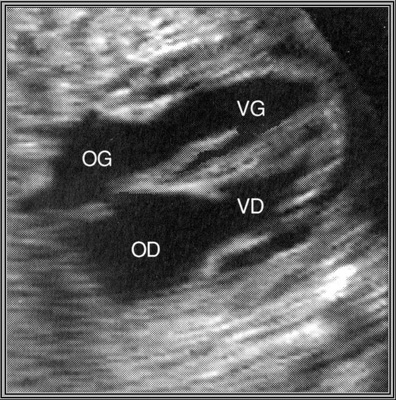

Concordance auriculo-ventriculaire

4 cavités